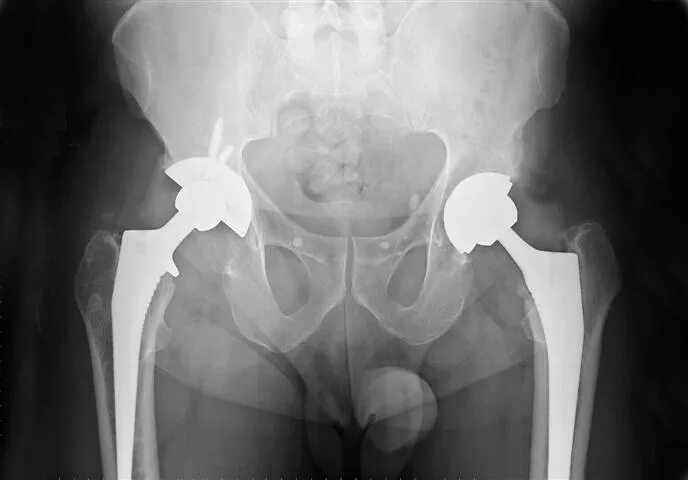

Нестабильность тазобедренного сустава